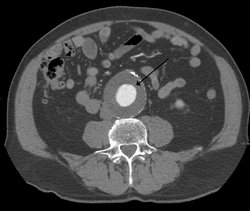

Abdominal aortic aneurysms (3,4 cm)

Abdominal aortic aneurysms (AAAs) are more common than their thoracic counterpart. One reason for this is that elastin, the principal load-bearing protein present in the wall of the aorta, is reduced in the abdominal aorta as compared to the thoracic aorta. Another is that the abdominal aorta does not possess vasa vasorum, the nutrient-supplying blood vessels within the wall of the aorta. Most AAA are true aneurysms that involve all three layers (tunica intima, tunica media and tunica adventitia). The prevalence of AAAs increases with age, with an average age of 65–70 at the time of diagnosis. AAAs have been attributed to atherosclerosis, though other factors are involved in their formation.[7]

The risk of rupture of an AAA is related to its diameter; once the aneurysm reaches about 5 cm, the yearly risk of rupture may exceed the risks of surgical repair for an average-risk patient. Rupture risk is also related to shape; so-called "fusiform" (long) aneurysms are considered less rupture-prone than "saccular" (shorter, bulbous) aneurysms, the latter having more wall tension in a particular location in the aneurysm wall.[10]

Before rupture, an AAA may present as a large, pulsatile mass above the umbilicus. A bruit may be heard from the turbulent flow in the aneurysm. Rupture may be the first sign of AAA. Once an aneurysm has ruptured, it presents with classic symptoms of abdominal pain which is severe, constant, and radiating to the back.[10]

The diagnosis of an abdominal aortic aneurysm can be confirmed by the use of ultrasound. Rupture may be indicated by the presence of free fluid in the abdomen. A contrast-enhanced abdominal CT scan is the best test to diagnose an AAA and guide treatment options.[11]